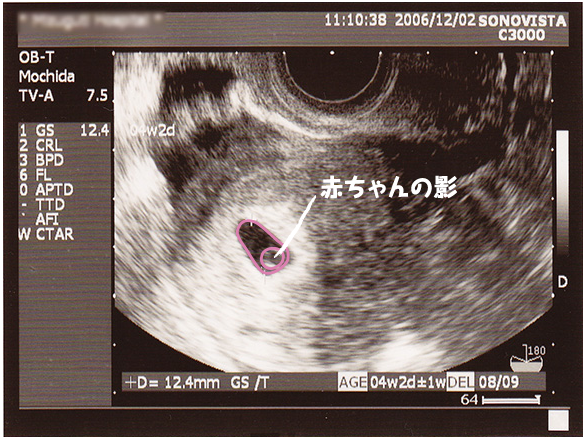

5 産科一般超音波検査 初期編 正常所見4 7週 日本産婦人科医会

5 産科一般超音波検査 初期編 正常所見4 7週 日本産婦人科医会

5 産科一般超音波検査 初期編 正常所見4 7週 日本産婦人科医会

5 産科一般超音波検査 初期編 正常所見4 7週 日本産婦人科医会